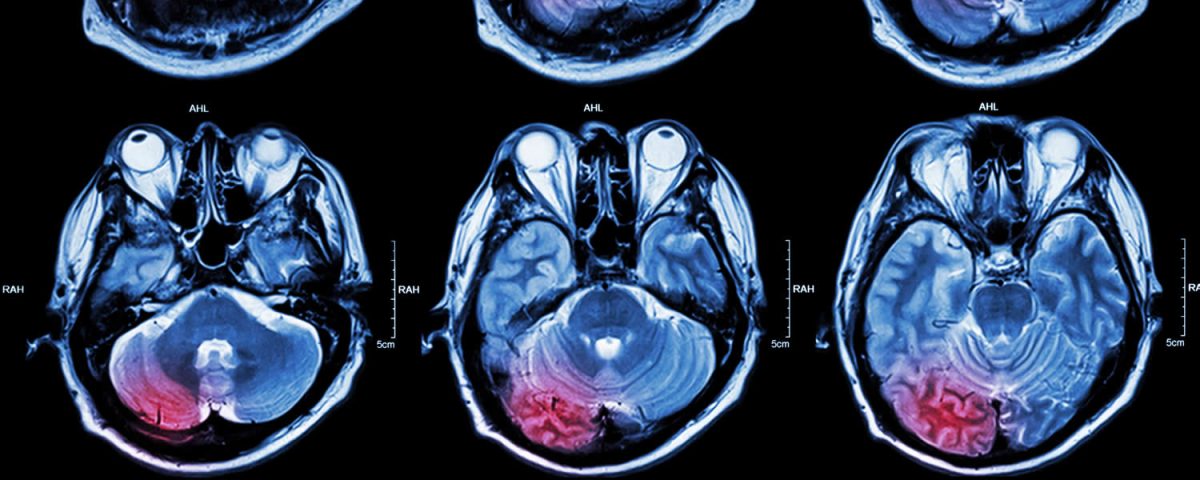

O AVC é um problema grave de saúde, e ocorre quando uma artéria do cérebro é obstruída por um coágulo ou rompe em algum ponto, provocando o extravasamento do sangue (hemorragia). Desta maneira, o AVC é conhecido no meio médico como AVC i, de isquêmico ou AVC h, de hemorrágico.

A prevenção do AVC se faz através da mudança de hábitos. A principal causa do AVC é a hipertensão arterial. As altas pressões dentro dos vasos promovem um enrijecimento dos mesmos, facilitando a progressão das placas de gordura no corpo inteiro, inclusive nos vasos do cérebro. Outra causa cardiológica comum de AVC é a fibrilação atrial, arritmia que gera trombos no coração e assim eles se deslocam, podendo se alojar nos pulmões (tromboembolismo pulmonar) ou no cérebro, ocasionando o AVC isquêmico.

Os principais sintomas do AVC é a perda de alguma função do corpo, seja cognitiva (deixar de falar) ou motora (desvio do lábio, perda de força súbita em algum lado do corpo). Ao presenciar alguém manifestando estes sintomas, a pessoa deve ligar imediatamente para o SAMU (192), e fazer um chamado de urgência. Quanto mais cedo a artéria for desobstruída, menor as sequelas. Tempo é cérebro!